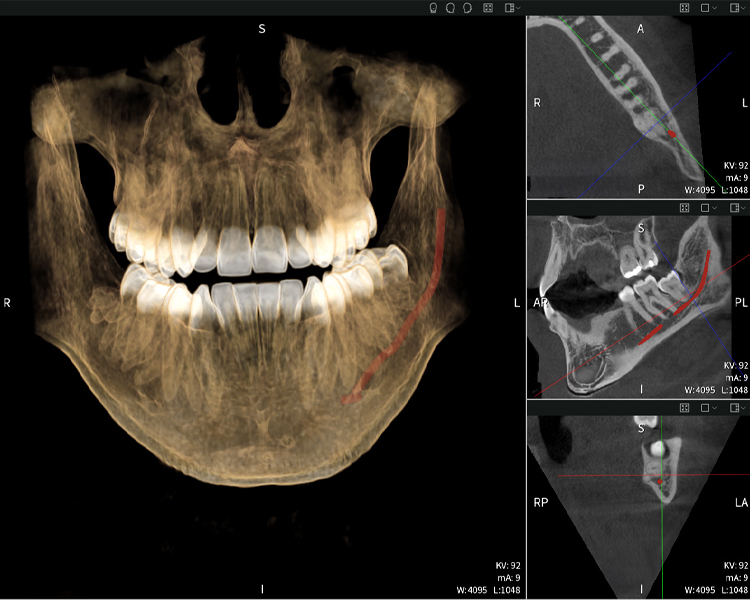

Abbildungen b–d zeigen verschiedene Ansichten einer 3D-Rekonstruktion des Unterkiefers und bieten eine umfassende Übersicht über die Anatomie des Unterkiefers, die Lage der Nerven im Verhältnis zu den Zähnen und ermöglichen die Beurteilung der Zahnsymmetrie und Ausrichtung.

Abbildung d zeigt den bereits vorbehandelte Zahn 48, dessen Krone entfernt wurde und dessen Wurzeln nahe am Nerv belassen wurden, was das hohe Risiko einer Nervenschädigung verdeutlicht.